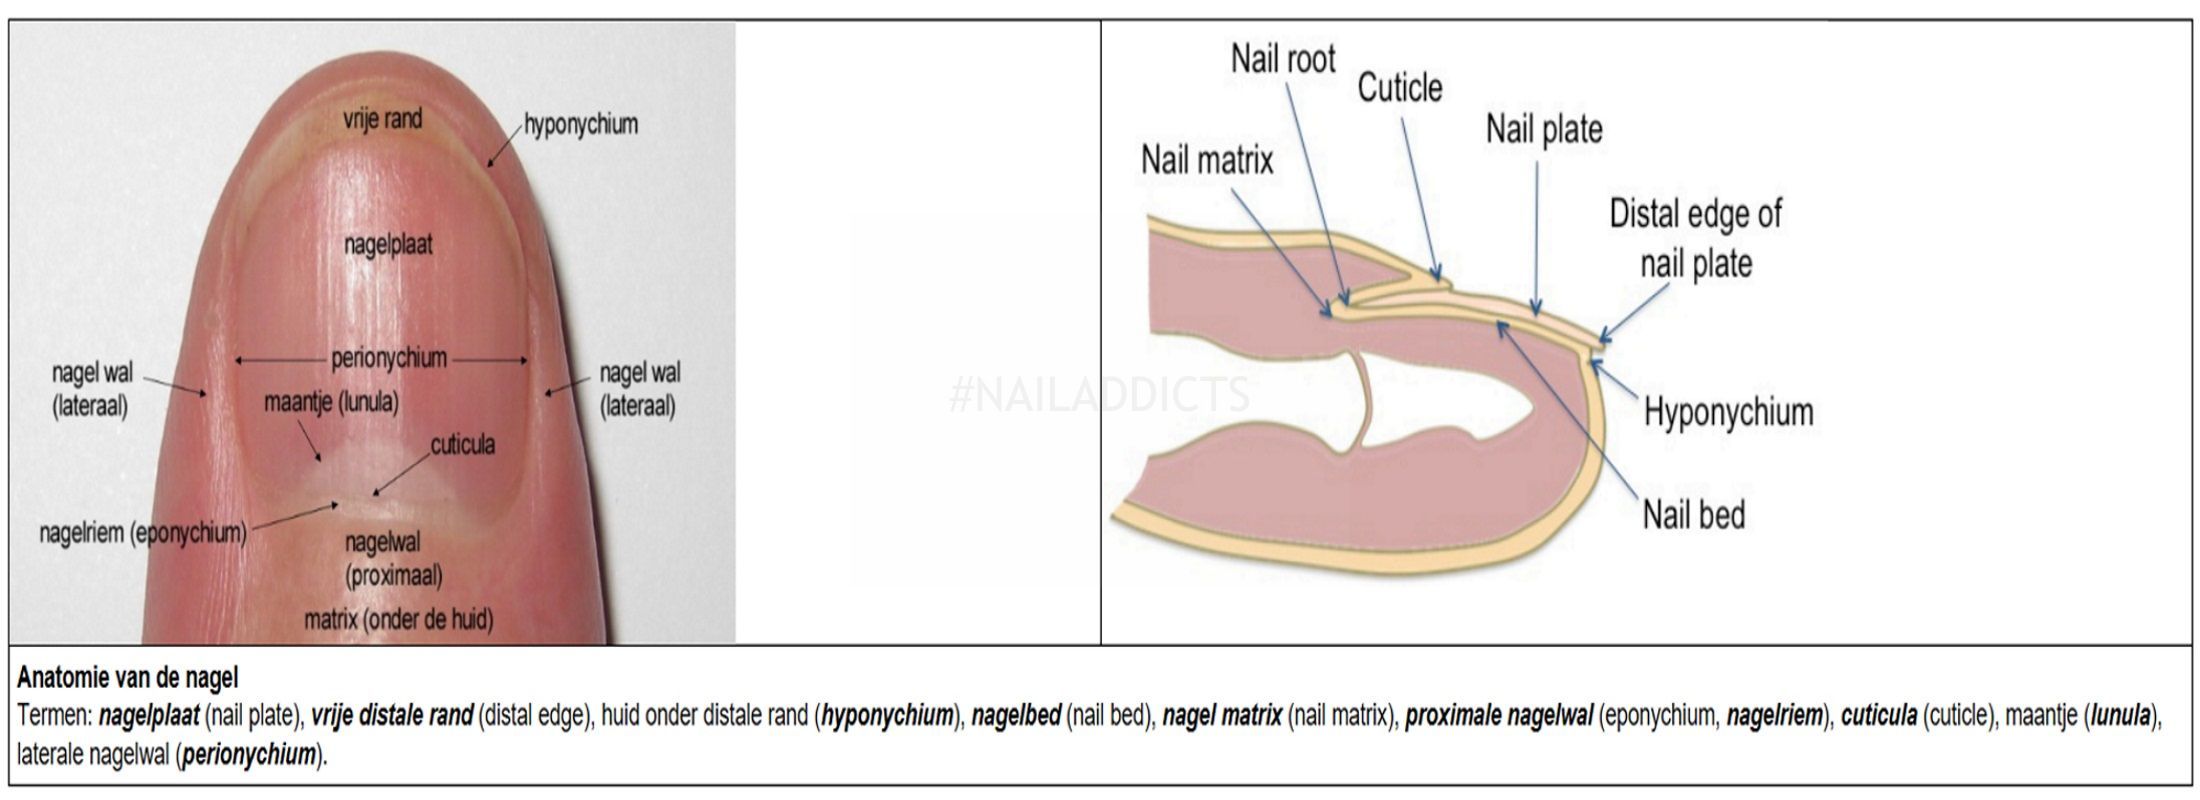

Een patiënt met deze afwijking heeft bolle nagels met bredere vingertoppen en geen nagelriemen. Je longen hebben een bijzondere anatomie en bevinden zich in je borstkas en worden omringd door je ribben. Dat wil zeggen dat we uit een verkleurde iris, of blauwgroene pus, of een bolle nagel, een hele wereld aan pathologie.

Enkele longaandoeningen, hartaandoeningen, huidaandoeningen en maagdarmaandoeningen gaan gepaard met dit symptoom. Mensen met hele bolle nagels, ook wel trommelstokvingers of horlogenagels genoemd, hebben nagels die over de vingertop heen groeien. Erg bleke of witte nagels ontstaan door ouder worden, maar het kan ook een teken zijn van serieuze aandoeningen, zoals bijvoorbeeld bloedarmoede, leverziekte, voedingsstoffentekort en hartfalen.

Trommelstokvingers of horlogeglasnagels zijn bolronde nagels en eindkootjes, welke worden geassocieerd met interne aandoeningen die gepaard gaan met onvoldoende doorbloeding (ischemie). But not sure were to start?. Normaalgezien is de afwijking niet pijnlijk, maar soms presenteert een patiënt zich met pijn in de vingertoppen.

Vormveranderingen (bolle, holle en kromme nagels) Trommelstokvingers (clubbed fingers), bolle nagels Bij trommelstokvingers zijn de nagels bolvormig, de hele eindkootjes zijn verdikt. Neem een kijkje op de beste bolle nagels longen in de foto’s hieronder en krijg ideeën voor uw fotografie!!!. De nagel drukt dan tegen de zijkant van de nagelwal.

Het is niet onverstandig om een afspraak te maken met uw huisarts wanneer u last heeft van bolle nagels. Bolle nagels ontstaan doordat u te weinig zuurstoftoevoer naar uw vingertoppen heeft. 4/mai/18 - Neem een kijkje op de beste bolle nagels longen in de foto’s hieronder en krijg ideeën voor uw fotografie!!!.

Dit is de reden waarom iedereen gebruiken Bolle Nagels Longen. Artsen spreken van ‘horlogeglasnagels’, vanwege de gelijkenis met een horlogeglas. Mooi verzorgde vingernagels zijn belangrijk voor je uitstraling en je zelfbeeld, maar ze zeggen ook iets over je gezondheid.

Kijkonderzoek in de longen (bronchoscopie) en biopsie U krijgt eerst plaatselijke verdoving met een spray of narcose. Bolle nagels komen vaak voor in combinatie met zogenaamde ‘ trommelstokvingers ‘. Hele bolle nagels van de vingers (trommelstokvingers).

Die strepen op de vingernagels vernietigen niet alleen het uiterlijk van de nagels. Symptomen en oorzaken horlogeglasnagels. Tunnelnagels of bolle nagels Met name de nagels van de grote teen kunnen bij een te smalle schoen onderhevig zijn aan te hoge druk en wrijving waardoor de nagel in de nagelwal kan graag ingroeien.